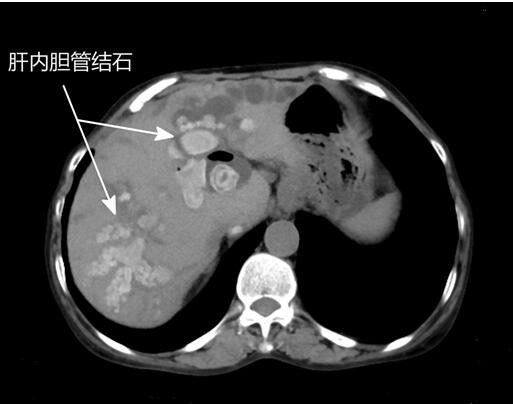

三、如何判断是否得了肝内胆管结石?

通过以下检查方可知晓:

常规体检:腹部彩超;

术前检查:腹部MRI 或CT。